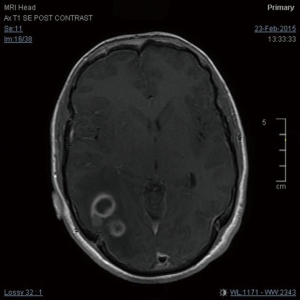

A 27-year-old gentleman presented with a 5-month history of tinnitus and increasing headaches in the occipital and orbital area. A CT scan was performed showing an intracerebral mass. An MRI head (Figure 1) was subsequently performed showing appearances consistent with a high-grade astroglial tumour with multifocal non-enhancing T2 hyperintense regions suggesting de-differentiation on a background of multifocal low-grade disease. Subtotal resection was performed and carmustine wafers were added to the surgical bed. Pathological tissue diagnosis was consistent with a right temporal lobe glioblastoma multiforme (GBM), IDH1 wild-type. The patient was treated with concurrent chemo-radiotherapy. In brief, intensity-modulated radiotherapy (IMRT) up to 60 Gy in 30 fractions to the right temporal lobe surgical bed with a margin and concurrent temozolomide (75 mg/m2/d × 7 d/week for 42 days). Five cycles of adjuvant temozolomide was given after chemo-radiation. The patient remained PS 0–1 during the treatment. Three weeks after finishing adjuvant temozolomide, the patient was admitted presenting left lower back pain, left lower limb heaviness and right lower limb sensory loss and numbness. At the time of admission neurological examination was normal except for sensory loss with a slightly impaired feeling in the lower right limb. The MRI of the brain showed mixed appearances, with response in the surgical bed but new foci in the corpus callosum and anterior periventricular region of the right hemisphere. The case was discussed at the Neuro Oncology Multidisciplinar Team meeting and advised to start second-line treatment with PCV (procarbazine, lomustine, and vincristine) was recommended. During this time, the patient had progressive neurological symptoms worsening with new leg weakness, unsteadiness, constipation, and difficulty passing urine. A spinal MRI (Figure 2) was performed showing multiple leptomeningeal and drop spinal metastases. The patient was treated with dexamethasone and underwent palliative radiation therapy to the thoracic and lumbosacral spine (from T12 to S3, 30 Gy in 10 fractions and from T5–T9, 20 Gy in 5 fractions). His clinical status continued to deteriorate declining and he was transferred to a palliative care service.